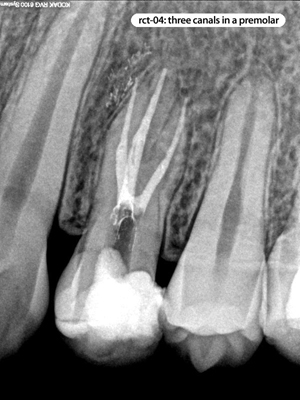

Root Canal Cases